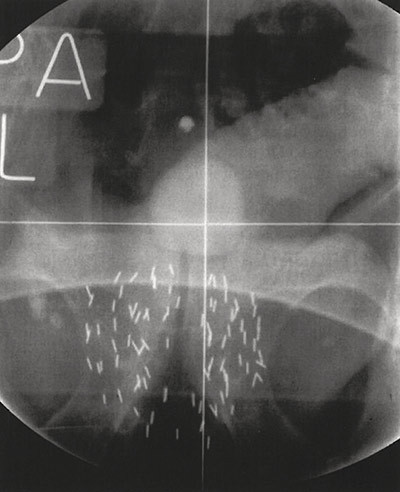

Enkelte ønsker imidlertid ikke å bli fulgt ubehandlet med en kreftdiagnose selv om sykdommen er stabil uten sykdomsprogrediering. Dersom slike pasienter skal behandles, bør metoden være effektiv og ha færrest mulig bivirkninger. Ultralydveiledet implantasjon av permanente radioaktive jodkorn (I-125) transperinealt inn i prostatakjertelen (lavdoserate brakyterapi – LDR-BT) er en metode som brukes i mange land hos disse pasientene (fig 1).

Lavdoserate brakyterapi, eller innvendig bestråling, er en høyteknologisk behandlingsprosedyre som tillater avsetning av svært høye kumulative stråledoser med kort rekkevidde i prostata (braky er gresk for kort), mens stråledosen som blir avsatt utenfor blir betydelig redusert. Stråledosen fra jodkornene avsettes gradvis i prostata i løpet av omtrent to måneder (fig 2).